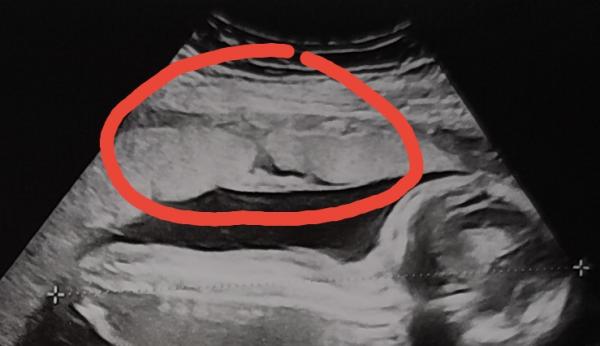

Huhu, erstmal vorweg, die Ärztin meinte gestern beim Ultraschall, die Plazenta sieht toll aus und ist nicht verkalkt. Als wir dann aber Zuhause die Bilder nochmal alle durchgesehen haben, fiel auf, dass die Plazenta in einem Bereich nicht durchgängig erscheint. Es sieht aus, als würde sich ein Riss quer durch die volle Dicke der Plazenta ziehen. Ich habe es mal im Bild rot eingekreist. Mir ist klar, dass meine Ärztin sicher etwas gesagt hätte, wenn etwas nicht in Ordnung wäre. Aber sie ist auch nur ein Mensch und vielleicht hat sie es übersehen? Die Plazenta hatte sie schon vorher ausreichend angeschaut, vielleicht war die Stelle da aber nicht zu sehen sondern nur lediglich in dem beigefügten Querschnitt? Oder möglicherweise hat sie es gesehen aber nichts gesagt, um uns nicht unnötig zu beunruhigen, weil es vielleicht harmloser ist als es für einen Laien aussieht? Kennt ihr das vielleicht von euren Ultraschallbildern und wisst, was es damit auf sich hat? Ich habe etwas von sogenannten Plazentaseen gelesen, was harmlose mit Blut der Mutter gefüllte Hohlräume sind. Für mich sieht das aber anders aus, weil es eben nicht wie für Gefäße im Ultraschall typisch kreisförmig aussieht, sondern wirklich wie ein Riss. Komisch finde ich generell, dass der an die Gebärmutterwand angrenzende Bereich der Plazenta nicht (weiß) aussieht, wie der Rest der Plazentastruktur, ich hoffe ihr versteht wie ich das meine.. Viele Grüße,  Susuba 19+0

Das ist ein Gefäß.